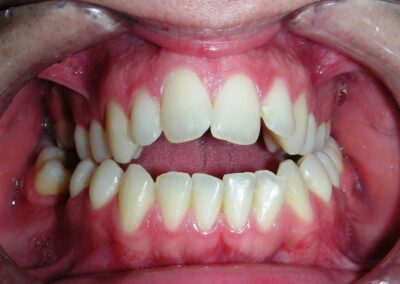

The patient presented with an anterior open bite, characterized by the absence of vertical overlap between the upper and lower incisors, and bilateral posterior crossbite. Extraoral examination revealed a vertically long facial pattern with an increased lower third of the face. The profile is convex with a retruded chin, indicating sagittal and vertical skeletal imbalances. We find also the inclined bipupillary line, which corresponds to facial asymmetries and altered occlusal plane.

Intraoral Examination:

Absent #16, #36 and #46 , No Angle molar relationship . Projection of canines axes in class II relationship . Anterior open bite: Over Bite – 8 mm). Bilateral posterior crossbite: Involvement of upper posterior sectors with inverted buccal-lingual relationship. Moderate Crowding at the level of the upper and lower incisors. Acceptable Oral Hygiene with no periodontal issues